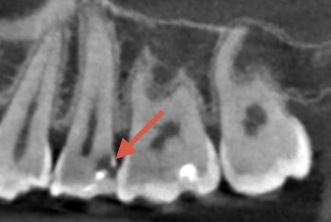

40代男性 上顎第二小臼歯が2次カリエス

口腔内/レントゲン画像

下の部分的なレントゲンになります。

青い部分が虫歯になり、赤色の歯の神経との距離がかなり近くもしくは虫歯で感染が起きている場合があります。痛みなどの症状がなかったため、MTAセメントを使用し神経保護を行なっていきます。